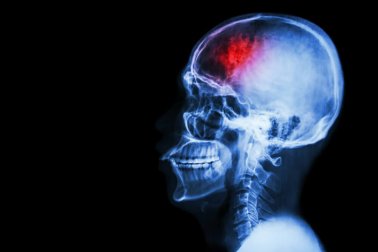

O acidente vascular cerebral ou derrame ocorre quando o suprimento de sangue para uma região do cérebro é cortado, o que pode causar danos e até a morte dos neurônios. Para evitá-lo, neste artigo indicamos 7 medidas preventivas contra o AVC.

O acidente vascular cerebral é uma doença cerebrovascular que afeta os vasos sanguíneos que fornecem sangue ao cérebro. Um AVC ocorre quando um vaso sanguíneo que leva sangue ao cérebro se rompe ou é bloqueado por um coágulo ou outra partícula.

Devido a esse colapso ou bloqueio, parte do cérebro não recebe o fluxo de sangue, oxigênio e glicose necessário. A consequência é que as células nervosas da área afetada do cérebro não recebem oxigênio e, portanto, não podem funcionar e morrem depois de alguns minutos.